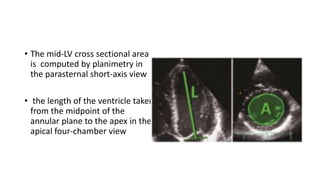

• The mid-LV cross sectional area

is computed by planimetry in

the parasternal short-axis view

• the length of the ventricle taken

from the midpoint of the

annular plane to the apex in the

apical four-chamber view